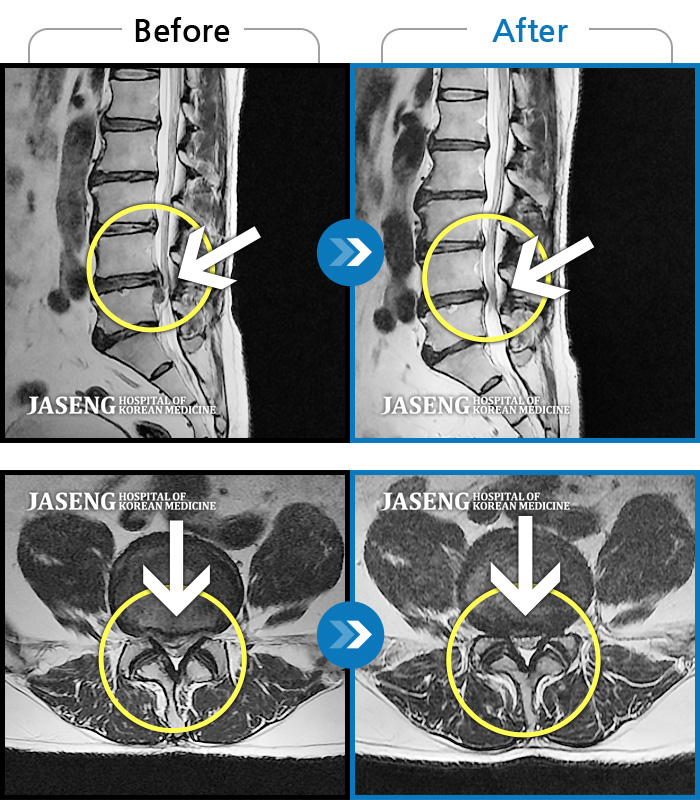

Before

After

환자에게 사전 동의를 받아 동일 조건에서 촬영되었습니다.

개인에 따라 치료 후 부작용이 발생할 수 있으니 의료진과 상담 후 치료를 진행하시기 바랍니다.